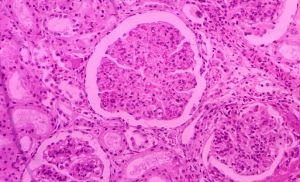

1.光鏡 多數為系膜增生性或I型系膜毛細血管性腎小球腎炎,部分為毛細血管內增生或局灶增生性賢淑小球腎炎,偶見新月體性腎小球腎炎。

2.電鏡可見毛細血管內皮下有電子緻密物沉積,在腎小球沉積物中可找到感染菌的抗原。

3.免疫螢光顯示IgG、IgM及C3呈顆粒狀或團塊狀沉積於毛細血管壁和系膜區。